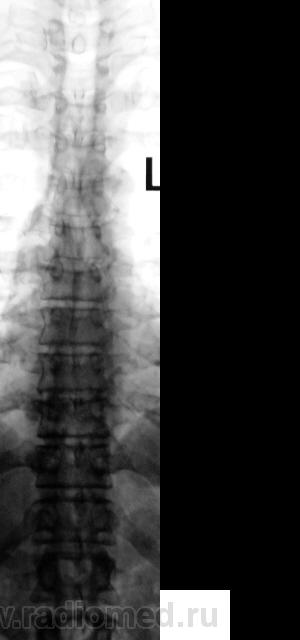

Если это женщина,старше 60 лет-обычная центральная грыжа Шморля при синильном остеопорозе.

Нет. Это мужчина. Возраст - 50 лет.

Тогда все равно грыжа Шморля :))))))))

Продольные полоски в телах позвонков тоже встречаю относительно часто. В книгах встречал 2 версии их происхождения: рудимент питающих артерий и форма перестроечной б-ни.

Похоже на большую грыжу, но мне кажется, что в ней что-то лежит, как сахарок тает? Не получится ли продолжения процесса?

Не в коем случае нельзя сбрасывать со счетов ТБС поражение позвонка. Создается впечатление о переходе процесса на вышележащий позвонок.

... тогда Фанарджяна (по костям) - в утиль! Какая перестроечная болезнь - во всех позвонках, строго по центру!?

Конечно же, рудимент. пит. артерии!